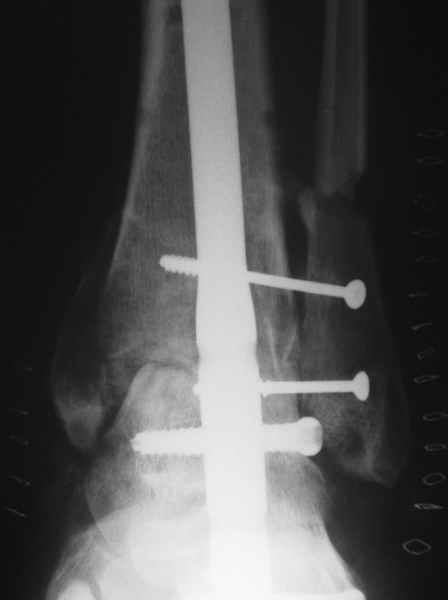

Конечно. Но если нет повода трогать подтаранный сустав, может, делать не через него, а так?

Кликните для загрузки файла ankle.jpg

12KB (12702 bytes)

В принципе можно и так, но тогда нет смысла загонять гвоздь. Можно 2-3 крепких шурупа. А так как-то уж слишком.

Гвоздь через один сустав - слищком, а через два, причем один интактный - не слишком? :-)

Можно и винтами. Представляется, что это все-таки менее надежно, чем гвоздь - винты под разными углами надо проводить, и не по оси нагрузки они получатся. То есть динамизации такой, как на гвозде, не достичь. Винты, насколько я знаю, комбинируют с аппаратом, чтобы сократить время пребывания в нем.